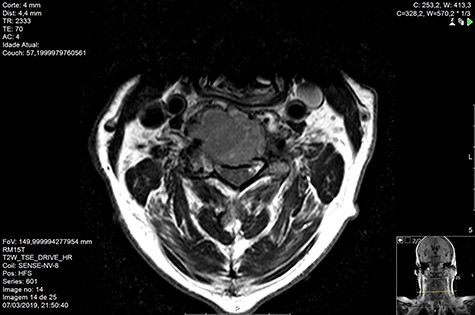

Computed tomography (CT) (Figs 1–3) and magnetic resonance imaging (MRI) (Figs 4–6) of the cervical spine were performed and revealed a lytic lesion involving most of C4, C5 and C6 vertebral bodies with bilateral extension to the posterior spinal elements of C4 and C5 and complete disruption of C4-C5 and C5-C6 intervertebral discs.

The Spinal Instability Neoplastic Score (SINS) [4, 6, 7] for assessing spinal instability from metastatic disease was used and the lesion was deemed unstable (SINS 13), with impending risk of increased neurological damage.

Findings from laboratory tests (serum protein electrophoresis) led to the diagnosis of MM. The patient was placed on a Philadelphia c-spine collar and underwent local 3D external-beam radiotherapy (20Gy in five fractions).